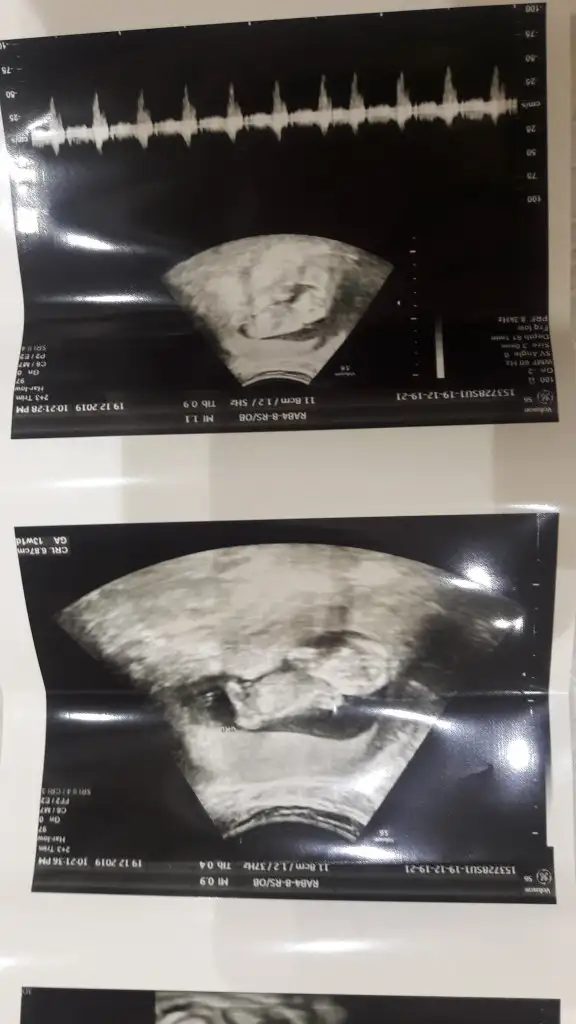

Erkek benim buyuk oglanindi. 4 hafta 10 hafta 14 haftalikKaç haftalık burada sagda ve kız buna göre

14 haftamı göremedim sadece keseye baktım. Geriside hiç birsey göremedimErkek benim buyuk oglanindi. 4 hafta 10 hafta 14 haftalik

4+6 olan usg var gerisi hiç belli degil onlarda küçük usg dedimErkek benim buyuk oglanindi. 4 hafta 10 hafta 14 haftalik

Erkekbu resimde nub yukarıda sanki

Kaç haftalık 6 7 olmalı erkek keseye göreKese konumundan bakabilir misiniz rica etsem